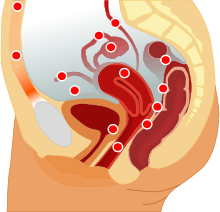

Localization

Most endometriosis is found on these structures in the pelvic cavity:[43]

- Ovaries (the most common site)

- Fallopian tubes

- The back of the uterus and the posterior cul-de-sac

- The front of the uterus and the anterior cul-de-sac

- Uterine ligaments such as the broad or round ligament of the uterus

- Pelvic and back wall

- Intestines, most commonly the rectosigmoid

- Urinary bladder and ureters

Rectovaginal or bowel endometriosis affects approximately 5-12% of women with endometriosis, and can cause severe pain with bowel movements.[44]

Endometriosis may spread to the cervix and vagina or to sites of a surgical abdominal incision, known as "scar endometriosis."[45] Risk factors for scar endometriosis include previous abdominal surgeries, such as a hysterotomy or cesarean section, or ectopic pregnancies, salpingostomy puerperal sterilization, laparoscopy, amniocentesis, appendectomy, episiotomy, vaginal hysterectomies, and hernia repair.[46][47][48]

Endometriosis may also present with skin lesions in cutaneous endometriosis.

Less commonly lesions can be found on the diaphragm. Diaphragmatic endometriosis is rare, almost always on the right hemidiaphragm, and may inflict cyclic pain of the right shoulder just before and during a menstrual period. Rarely, endometriosis can be extraperitoneal and is found in the lungs and CNS.[49]